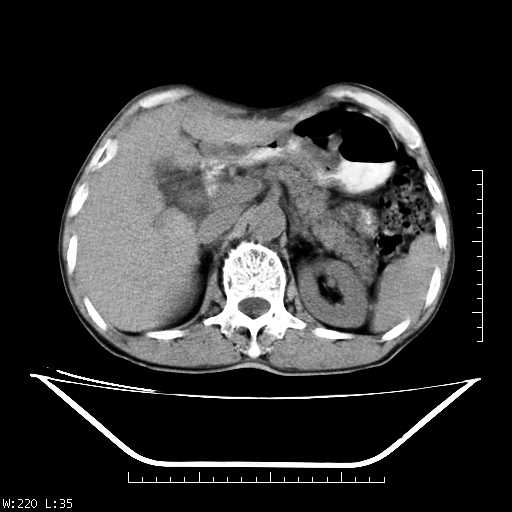

男,70,右上腹痛两月,有乙肝病史,b超提示肝占位,ct如下,请会诊。

补充:该患者afp9.24

肝右叶类圆型密度减低影,密度不均,边界清晰其内可见更低密度影,腹膜后可见小淋巴结肿大,增强扫描动脉期病灶明显强化,静脉期及延时扫描见强化不明显,快进快出表现。

1.肝右叶低密度影考虑为肝癌;

2.肝转移待除外。

平扫呈低密度占位,动脉期斑片状明显强化,病灶边缘清晰,见假包膜;门脉期呈低密度,符合肝癌快进快出强化特征

补充:该患者afp 9.24,似乎与原发性肝癌不符合,另胰头区结构正常吗?请大家继续发表高见。